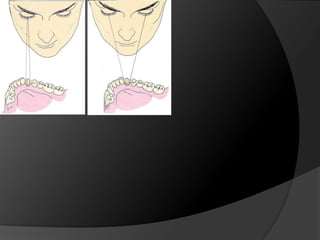

El análisis para seleccionar la ubicación de la línea de terminación se enfoca en 2 componentes:Estética vs HigieneExtensión mínima dentro del surco gingivalDisimular la zona de asentamientoFacilitar la higiene del pacienteNecesidad de aumentar la retención y estabilidadLínea de Sonrisa